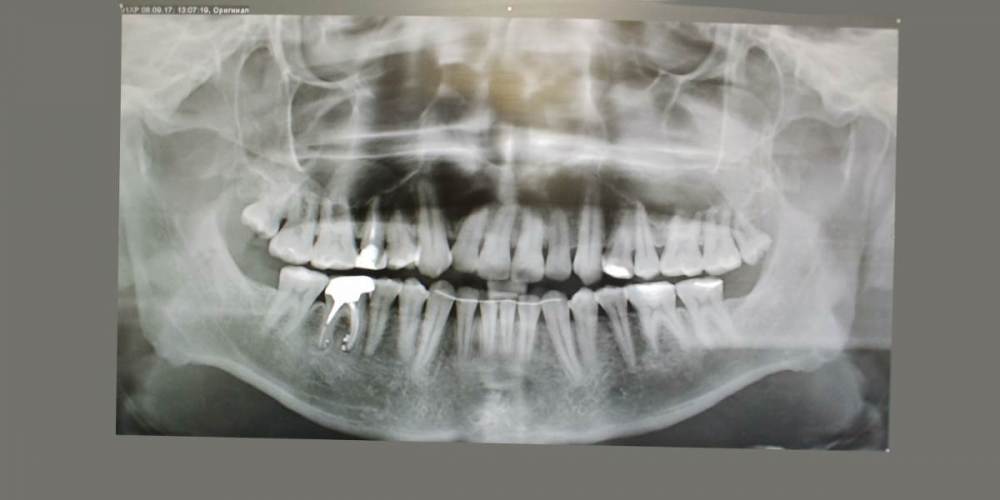

kamacho Опубликовано 15 февраля, 2024 Поделиться Опубликовано 15 февраля, 2024 Уважаемые специалисты. Беспокоит 15 зуб Коронка стоит 2-4 года. Беспокоит переодическая кровь при чистке флосом и иногда неприятный запах между 16 и 15 зубом (как правило ближе к 15ому) Иногда теряю обоняние. Обильный серый налет на языке по утрам. После ирригатора, флоса и тщательной чистки обоняние возращается. В клинике сказали что коронка прилегает хорошо и выступов нету(посещал дважды). Если будет возможность дополню тему прицельными снимками. 1)Скажите пожалуйста, есть ли показания для лечения этого зубика? 2)Могут ли не до конца пролеченные корни вызывать такую симптоматику ? 3)И если да то что лучше сделать? Стоит ли заменить на имплант ? Так же буду очень признателен если кто-то предложит специалиста Москве к которому можно было бы обратиться. Немножко предыстории и описание кт если вам интересно. Корни пломбировали где-то лет 10-15 назад. Сначала закрывали пломбой, которая потемнела. Обратился по поводу эстетики в клинику, терапевт хотела перелечить каналы, но когда сняла пломбу увидела цемент и сказала что не получится. Предложили закрыть коронкой и не трогать. С тех пор обращатся в клиннику дважды с жалобами про кровь и трудность гегиены. Предлагали акуратней пользоватся нитью и чаще следить за гегиеной. 1.5 зуб — депульпирован. Коронковая часть: восстановлена искусственной коронкой. Вариант строения: два корня, два канала. Обтурация: ЩК - установлен штифт на 1⁄2 длины корня, далее канал обтурирован пломбировочным материалом, не доходя до верхушки корня на 2,4 мм. НК - установлен штифт на 1⁄2 длины корня, далее канал обтурирован пломбировочным материалом, не доходя до верхушки корня на 2,9 мм. Периодонтальное пространство: не изменено. Пародонт: без особенностей. Ссылка на комментарий

Carioznik Опубликовано 25 февраля, 2024 Поделиться Опубликовано 25 февраля, 2024 15.02.2024 в 18:43, kamacho сказал: есть ли показания для лечения этого зубика? По идее есть, но нужно разбираться 15.02.2024 в 18:43, kamacho сказал: Могут ли не до конца пролеченные корни вызывать такую симптоматику ? Нет 17 часов назад, kamacho сказал: Между 14 и 15 зубом, это убыль фуркации Нет. Похоже, что на 14 есть кариес. Возможно это и причина кровоточивости и запаха. Но нужно смотреть настоящую КТ , а не скрины. 18 часов назад, kamacho сказал: районе 37 ого зуба это артефакт или кариес ? Больше на артефакт похоже, но это не точно: нужно смотреть настоящую КТ , а не скрины 1 Ссылка на комментарий